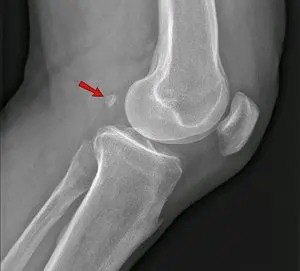

naar waar wijst het pijltje

naar de knieschijf of patella